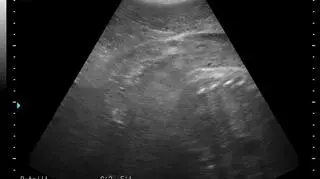

Agata, Ewa, Unda Marina i Ania spodziewają się potomstwa. Potwierdziło to pierwsze badanie USG, które przeszły foki. Nowi podopieczni pojawią się w helskim fokarium na przełomie lutego i marca.

Dobra nowinę ogłosili pracownicy Stacji Morskiej UG na jednym z portali społecznościowych, gdzie umieścili pierwsze zdjęcia maluchów.

- Po oddaniu do użytku najgłębszego basenu hodowlanego, udało nam się przeprowadzić badania USG w dogodnym dla zwierząt i opiekunów miejscu. Z radością więc informujemy, że tego roku wszystkie nasze cztery samice spodziewają się potomstwa - napisali.